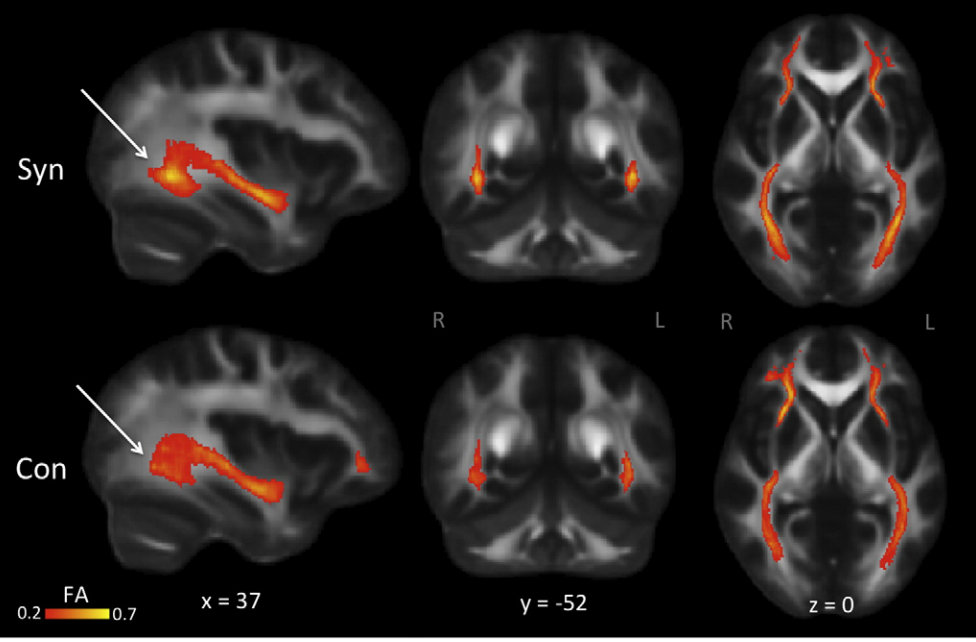

Schwettmann SE, Kadipasaoglu CM, Ma WJ, Eagleman DM (under review). Implicit mapping of musical relationships onto color space in chord-color synesthesia.